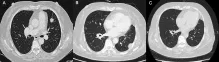

为了尽快控制病情,张阿姨接受了完全切除术,然而不幸的是,手术后不久就出现了转移,并且由于她的生长抑素受体表达极低,生长抑素类似物和肽受体放射性核素治疗等常规手段均无法应用,只能不断尝试各类化疗药物。让医生束手无策的是,在使用了包括卡铂、依托泊苷、卡培他滨、替莫唑胺、紫杉醇在内的多种化疗药物,以及依维莫司和阿特珠单抗等治疗方案后,肿瘤仍在疯狂增长,张阿姨病情持续恶化,出现无数皮下结节、左侧胸膜转移、多发性骨转移和脑转移等严重状况...

奇迹就这样发生了,治疗仅1个月迅速起效,张阿姨所有转移性肺病灶实现完全缓解。更令人欣喜的是,从开始接受恩曲替尼治疗至今,已持续获益至少一年,目前治疗仍在顺利进行中。